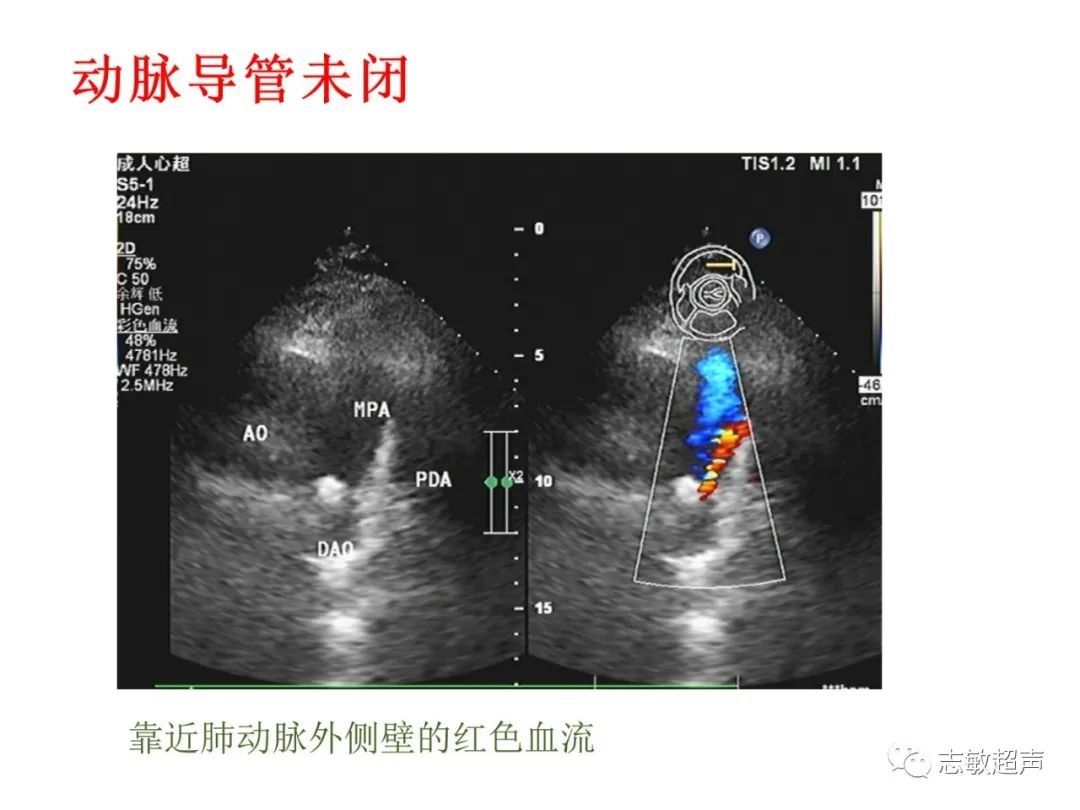

3.动脉导管未闭